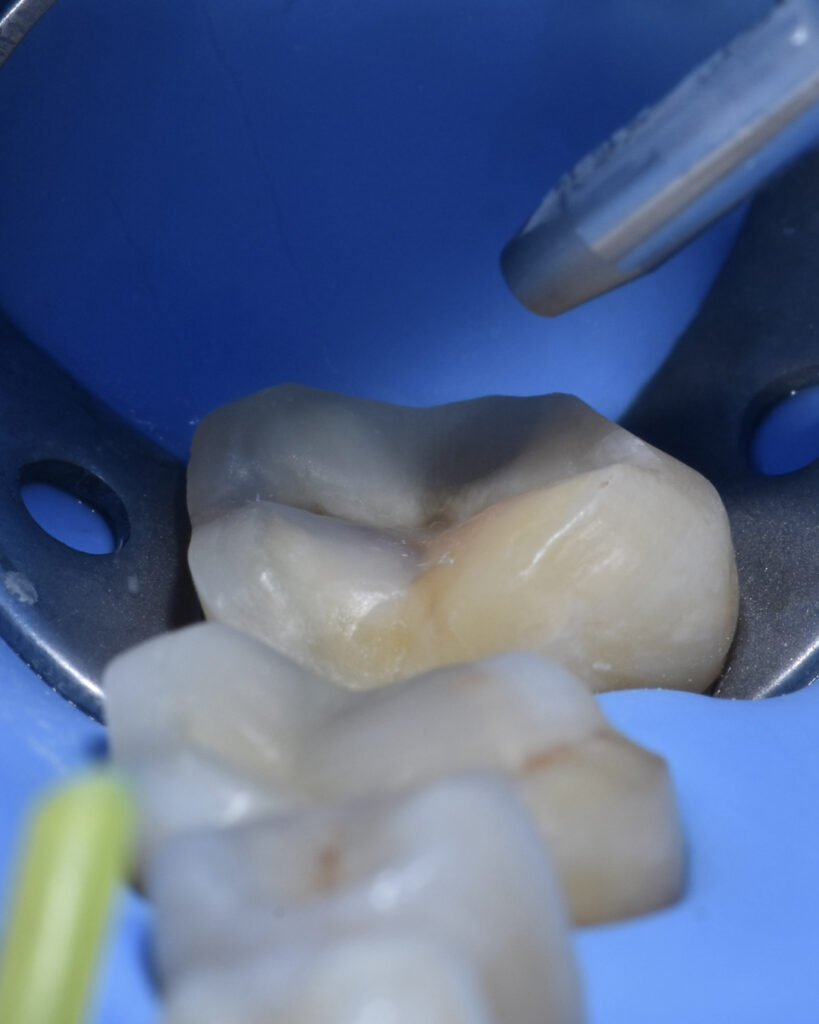

Tooth 3.6 was severely compromised and was managed with endodontic treatment, deep margin elevation, and an indirect adhesive restoration with full cuspal coverage using a lithium disilicate overlay.

Adhesive cementation was performed using preheated composite resin.